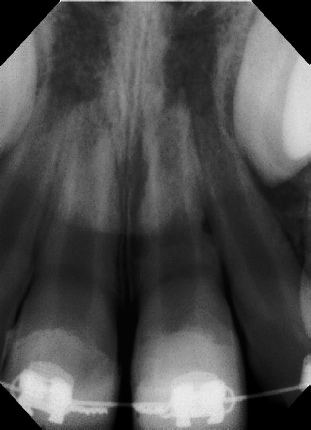

Cvek Pulpotomy 12 mos. Post-op Apexogenesis